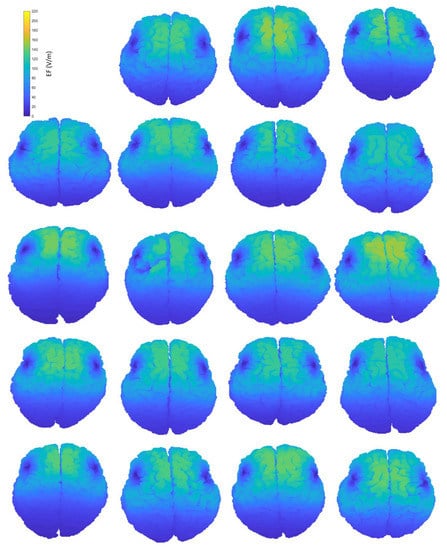

A simple visualization of the computed EF on the brain suffices to show the interindividual differences of the induced distributions, resulting from anatomical variations (Figure 2). Natural space coordinates were selected to highlight the morphology diversity that clinicians encounter during a TMS session. The distinctive characteristics of participants, such as the shape and size of their head, or even the head pose during the TMS session, have the potential to change the coil fitting and alter the stimulation’s outcome, influencing both the stimulated area and the magnitude of stimulation. This study focuses on parameters that can be measured and attempts to associate the stimulation characteristics with four of them, including age and total volumes of head, CSF (excluding the ventricles) and brain. Furthermore, homogeneous models are not affected by the electrical conductivity distribution, which is present only in anatomical models, carrying the information of tissue distribution. Therefore, the variation of the EF in homogeneous models reflects mainly the effects of head shape and size, whereas the variation of the EF in anatomical models incorporates the effect of individual tissue anatomy.

Figure 2.

Interindividual variability of the induced EF distributions visualized in subject brains, containing both grey and white matter, when the H-coil is placed at the central position. Head and brain anatomy affect the area and magnitude of stimulation. Brain coordinates are plotted on their natural space.

Figure 2 provides an indicative visual description of the variations in TMS-induced EFs for anatomical models and central coil positioning. Corresponding figures for homogeneous models and frontal coil positioning can be found in Appendix A. Complementary to EF visualization, Figure 3 and Figure 4 show the EF distributions in individual brains as violin plots and IQRs, providing a comparison across models and between their anatomical and homogeneous versions, for the two coil positions.